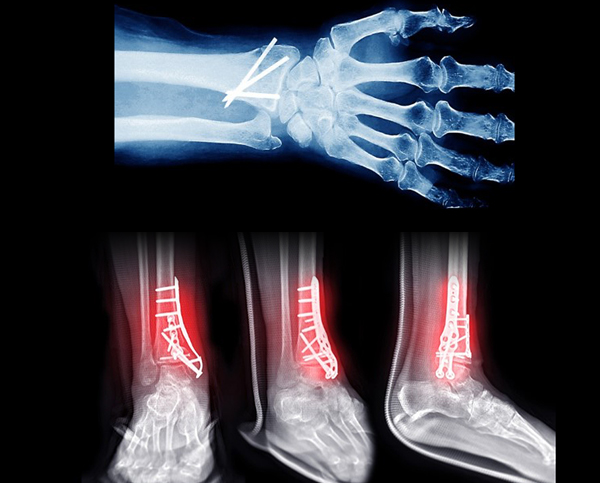

³Ñ¾îÁö°Å³ª ºÎµúÈ÷´Â »ç°í·Î ¼Õ¸ñÀ̳ª ¹ß¸ñ °ñÀýÀÌ ¹ß»ýÇÏ´Â °æ¿ì°¡ ¸¹½À´Ï´Ù. °ñÀýÀº ¿Ü»óÀ̳ª »ç°í·Î »À°¡ ºÎ·¯Áø

»óŸ¦ ¸»Çϸç, °ñÀýÀÇ ÇüÅÂ¿Í ¾ÈÁ¤¼º¿¡ µû¶ó Á¤È®ÇÑ Á¤º¹°ú °íÁ¤À» À§ÇÑ ¼ö¼úÀû Ä¡·á°¡ ÇÊ¿äÇÒ ¼ö ÀÖ½À´Ï´Ù.

°ñÀý ¼ö¼ú ½Ã¿¡´Â »À°¡ ¾ÈÁ¤ÀûÀ¸·Î À¯ÇÕµÉ ¼ö ÀÖµµ·Ï ±Ý¼ÓÆÇ, ³ª»ç, ÇÉ, ¿ÍÀÌ¾î µîÀÇ ±Ý¼Ó ±â±¸¸¦ ÀÌ¿ëÇØ °ñÀý ºÎÀ§¸¦ °íÁ¤ÇÕ´Ï´Ù. ÀÌ·¯ÇÑ ±Ý¼Ó

±â±¸´Â ´ëºÎºÐ À¯Áö °¡´ÉÇϳª, ÀÚ±Ø ¹× ÅëÁõÀÌ Áö¼ÓµÇ°Å³ª Ȱµ¿·®ÀÌ ¸¹Àº °æ¿ì¿¡´Â ¼ö¼ú ÈÄ 1~2³â »çÀÌ ±Ý¼Ó Á¦°Å ¼ö¼úÀ» °í·ÁÇÒ ¼ö

ÀÖ½À´Ï´Ù.